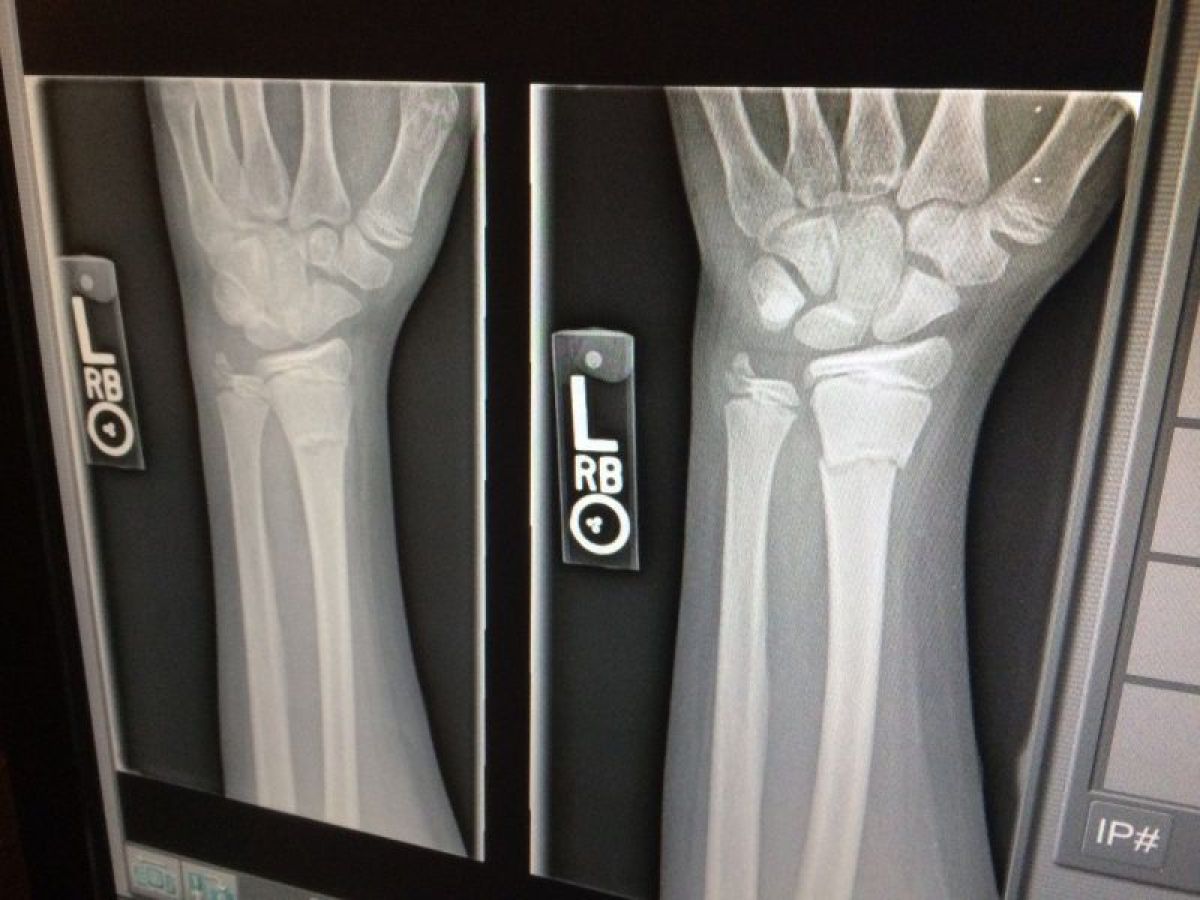

Kórházi látlelet – Törtek a csontok a mai ónos eső miatt Egerben is

A Heol.hu megkereste az egri Markhot Ferenc Kórházat, ahol egész döbbenetes számot mondtak csütörtök kora délután: csak délelőtt 75 beteget láttak el a Sürgősségi Betegellátó Osztály tarumatológiáján, "elsősorban balesetekből adódó sérülésekkel: kéz-, láb-, darabos törés, combnyaktörés, zúzódások".